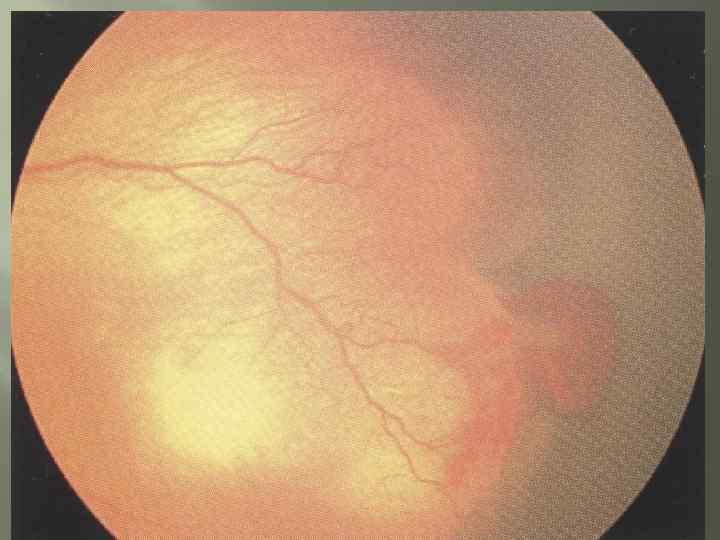

Классификация Частичная отслойка сетчатки; Полная отслойка сетчатки.

Классификация Частичная отслойка сетчатки; Полная отслойка сетчатки.

Диагностика Непрямая офтальмоскопия: Должна быть проведена с возраста 3 -4 нед и в последующем каждые 7 -10 дней, если имеется активная фаза заболевания. Впервые заболевание выявляется между 7 и 9 неделями жизни.

Диагностика Непрямая офтальмоскопия: Должна быть проведена с возраста 3 -4 нед и в последующем каждые 7 -10 дней, если имеется активная фаза заболевания. Впервые заболевание выявляется между 7 и 9 неделями жизни.